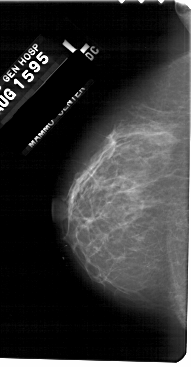

ics_version 1.0 filename A-1310-1 DATE_OF_STUDY 15 8 1995 PATIENT_AGE 48 FILM FILM_TYPE REGULAR DENSITY 1 DATE_DIGITIZED 7 7 1998 DIGITIZER HOWTEK 43.5 SEQUENCE LEFT_CC LINES 5491 PIXELS_PER_LINE 2851 BITS_PER_PIXEL 12 RESOLUTION 43.5 NON_OVERLAY LEFT_MLO LINES 5491 PIXELS_PER_LINE 3166 BITS_PER_PIXEL 12 RESOLUTION 43.5 NON_OVERLAY RIGHT_CC LINES 5491 PIXELS_PER_LINE 2926 BITS_PER_PIXEL 12 RESOLUTION 43.5 OVERLAY RIGHT_MLO LINES 5491 PIXELS_PER_LINE 2956 BITS_PER_PIXEL 12 RESOLUTION 43.5 OVERLAY |